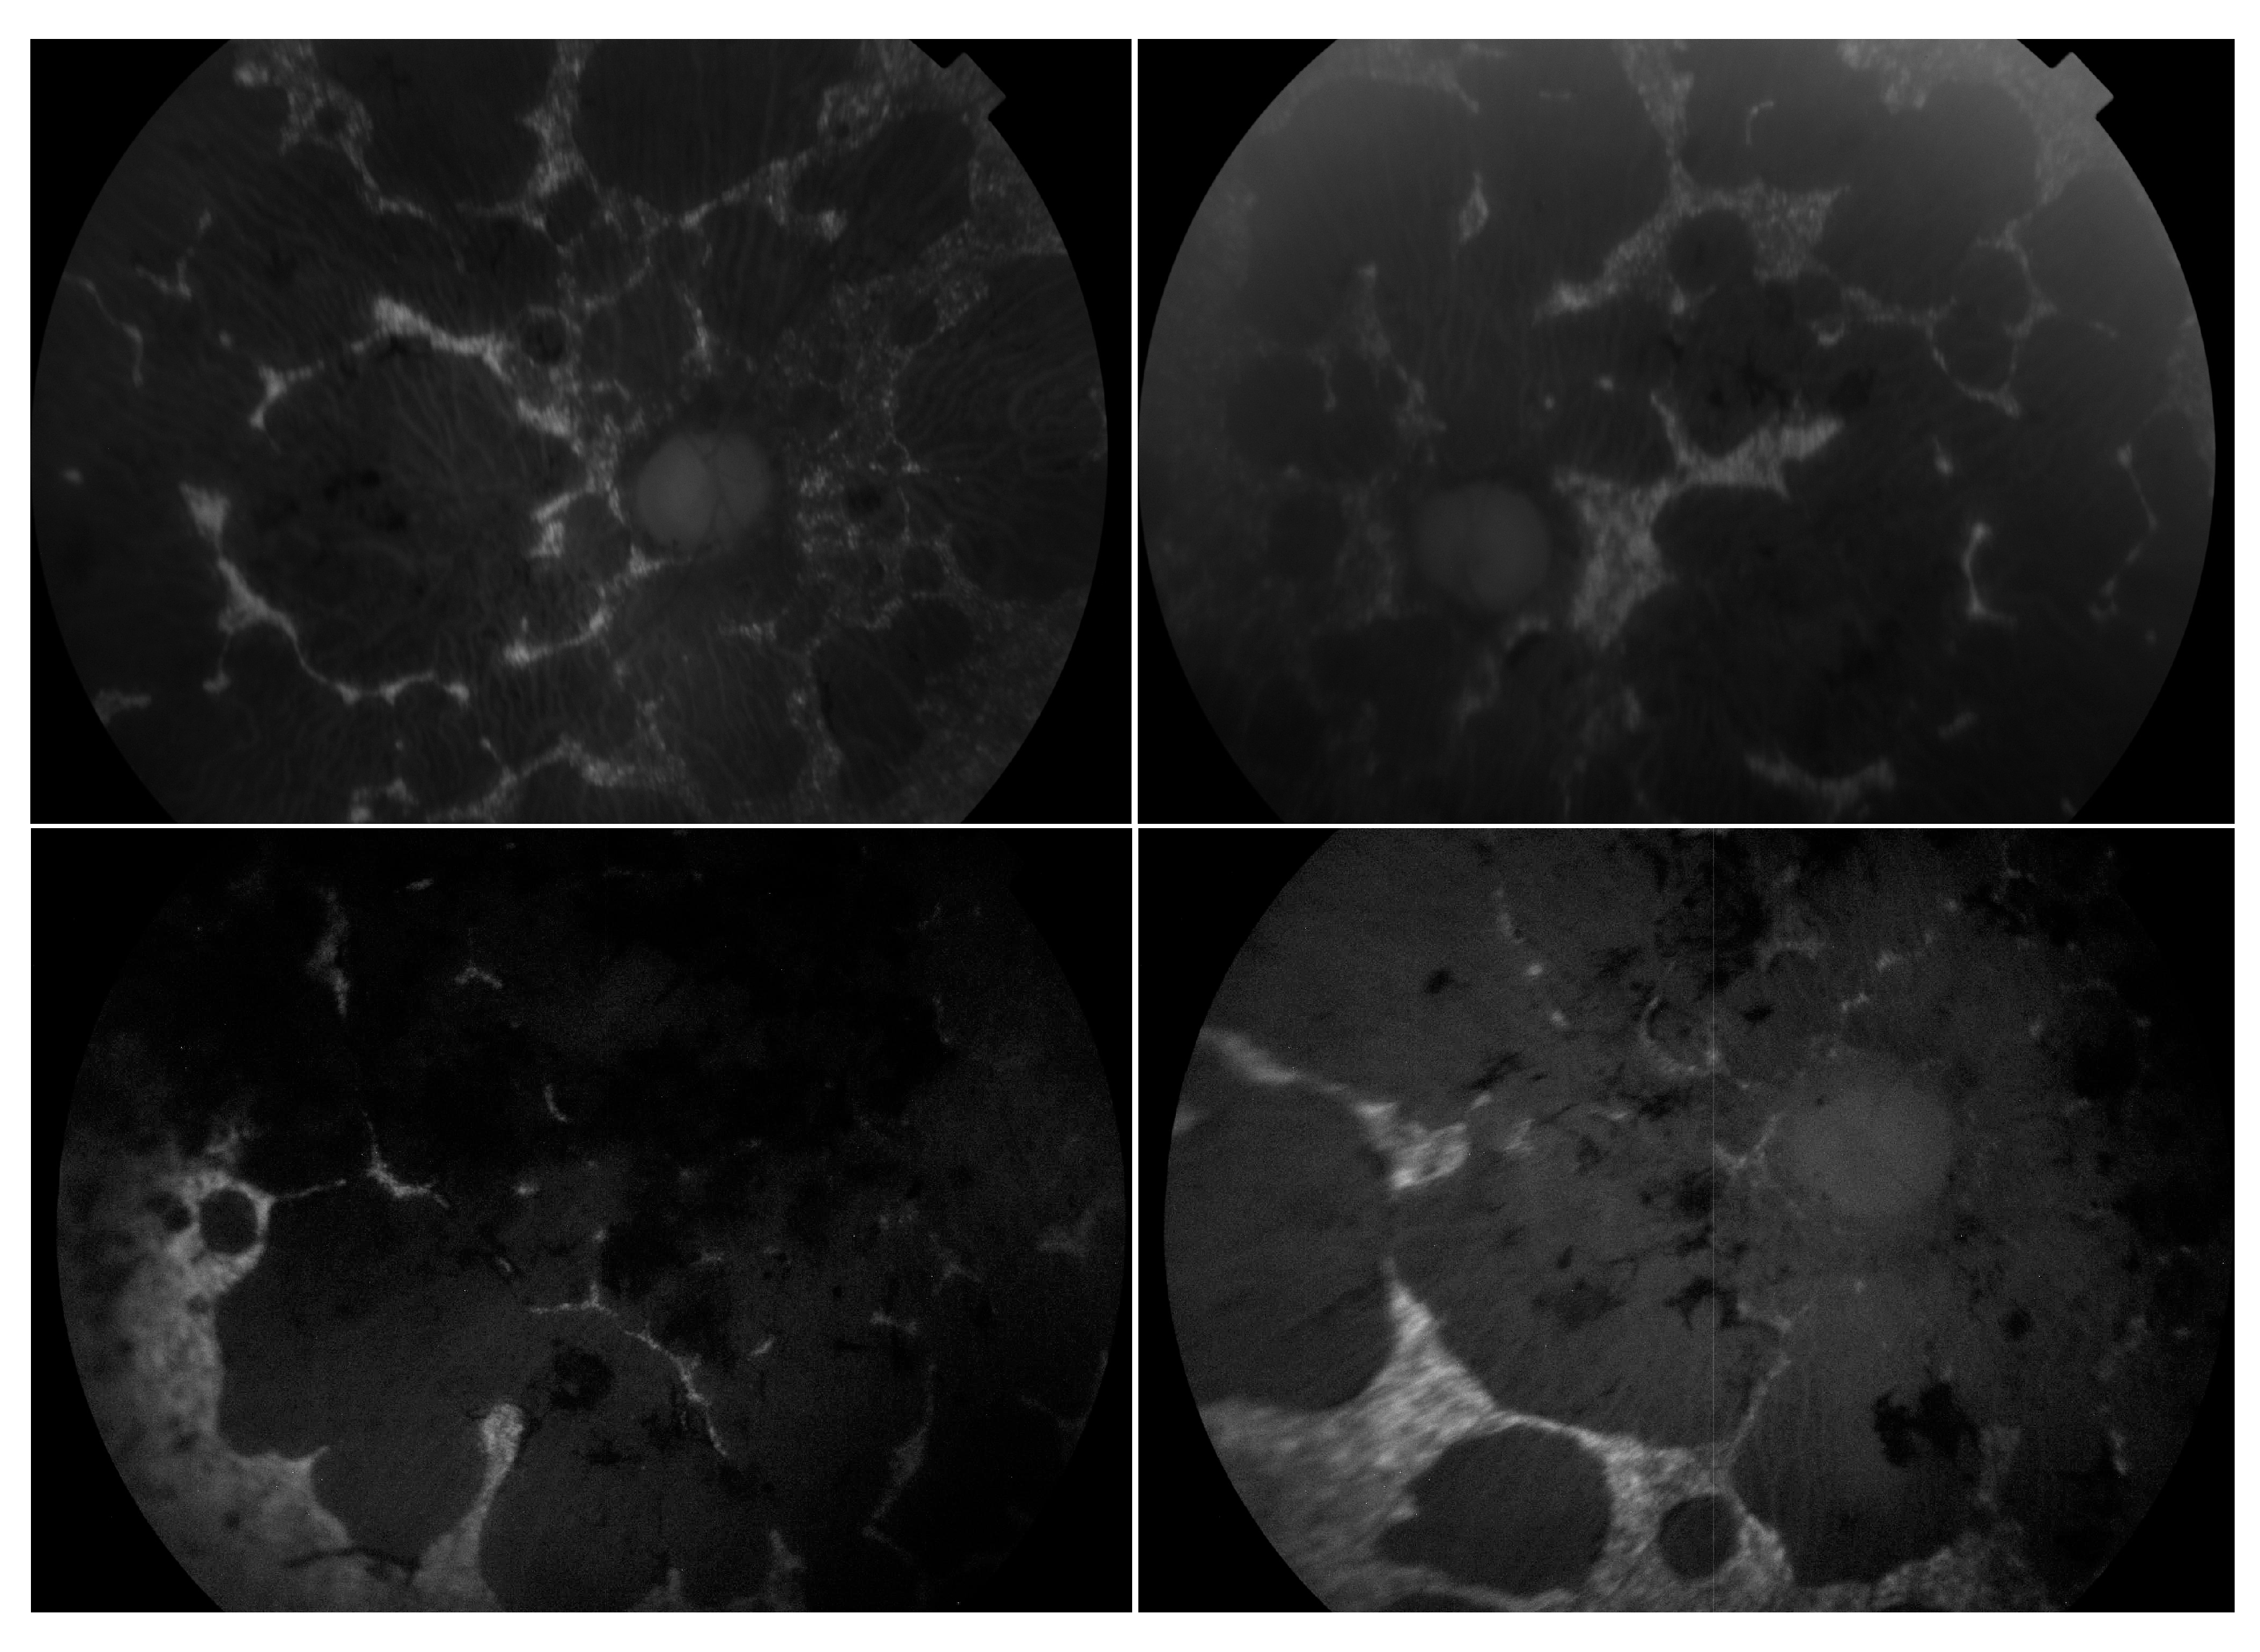

3.9. Choroideremia